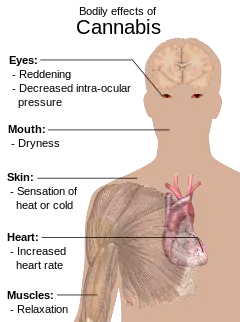

The NTFC reported several health effects of cannabis use, including risks that were identified as “major”, “majorly probable” and “majorly possible”.[3][2] There is less conclusive scientific evidence confirming the “majorly probable” and “majorly possible” risks of cannabis use, as it is difficult to measure the effects of cannabis use over the long term.[2]

The several “major” health effects of acute cannabis use (short-term effects of cannabis) found by the NTFC were:

- Anxiety, dysphoria, panic and paranoia

- Psychomotor impairment

- Increased risk of experiencing psychotic symptoms among those pre-exposed to psychosis

- Increased risk of lower birth weight babies

According to the NTFC the major effects of acute use only affected a minority of regular users.

The several “major probable” health effects of chronic cannabis found by the NTFC were:

- Respiratory diseases connected to smoking (chronic bronchitis and histopathological changes)

- Cognitive impairment (especially of memory and attention)

- Cannabis dependence syndrome

The long-term effects of cannabis remain uncertain.[11]

The other “major possible” risks of chronic use found by the NTFC were:

- Cancers of the oral cavity (pharynx and oesophagus)

- Lowered cognitive skills leading to reduced educational and occupational performance in adolescents

- Birth defects if cannabis is used during pregnancy (effects in pregnancy)

No clear evidence of these links have been provided.

The NTFC report concluded that there were three ‘high risk’ groups: adolescents (as use was most prevalent and could result in increased dependence), women of childbearing age and persons with pre-existing conditions.[2]